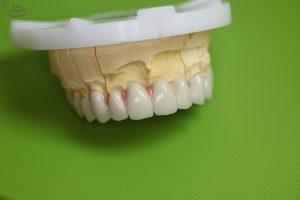

Az elkészült fémkerámia körhíd mestermintán. A magasabb esztétika érdekében a fogak közötti részen a fogtechnikus rózsaszín kerámiát használ, mely megegyezik az íny színével és takarja a fekete lyukakat. A fekete lyukak (fekete háromszöghatás), ami a fognyakak között alakul ki, rendkívül előnytelen esztétikai képet tud mutatni.

Az elkészült fémkerámia körhíd mestermintáról levéve szemből

Az elkészült fémkerámia körhíd mestermintáról levéve, alulnézetből